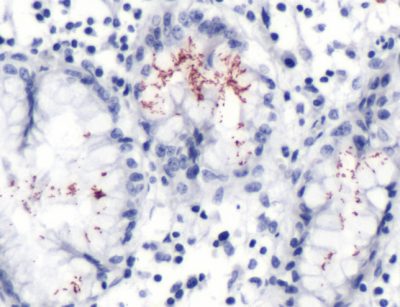

The H. (Helicobacter) pylori are known to cause chronic gastritis and peptic ulcers in humans. It is also associated with duodenal ulcers and could be involved in the development of adenocarcinoma or low-grade lymphoma of the mucosa associated with the lymphoid tissues of the stomach. It is designed for research purposes and has no known clone. The immunogen is the purified Helicobacter pylori. It also has a Rabbit IgG isotype and an undetermined epitope. It has no molecular weight, and it has been tested on humans.

The positive control is the Helicobacter pylori-infected tissue with cellular localization occurring in the Helicobacter pylori.